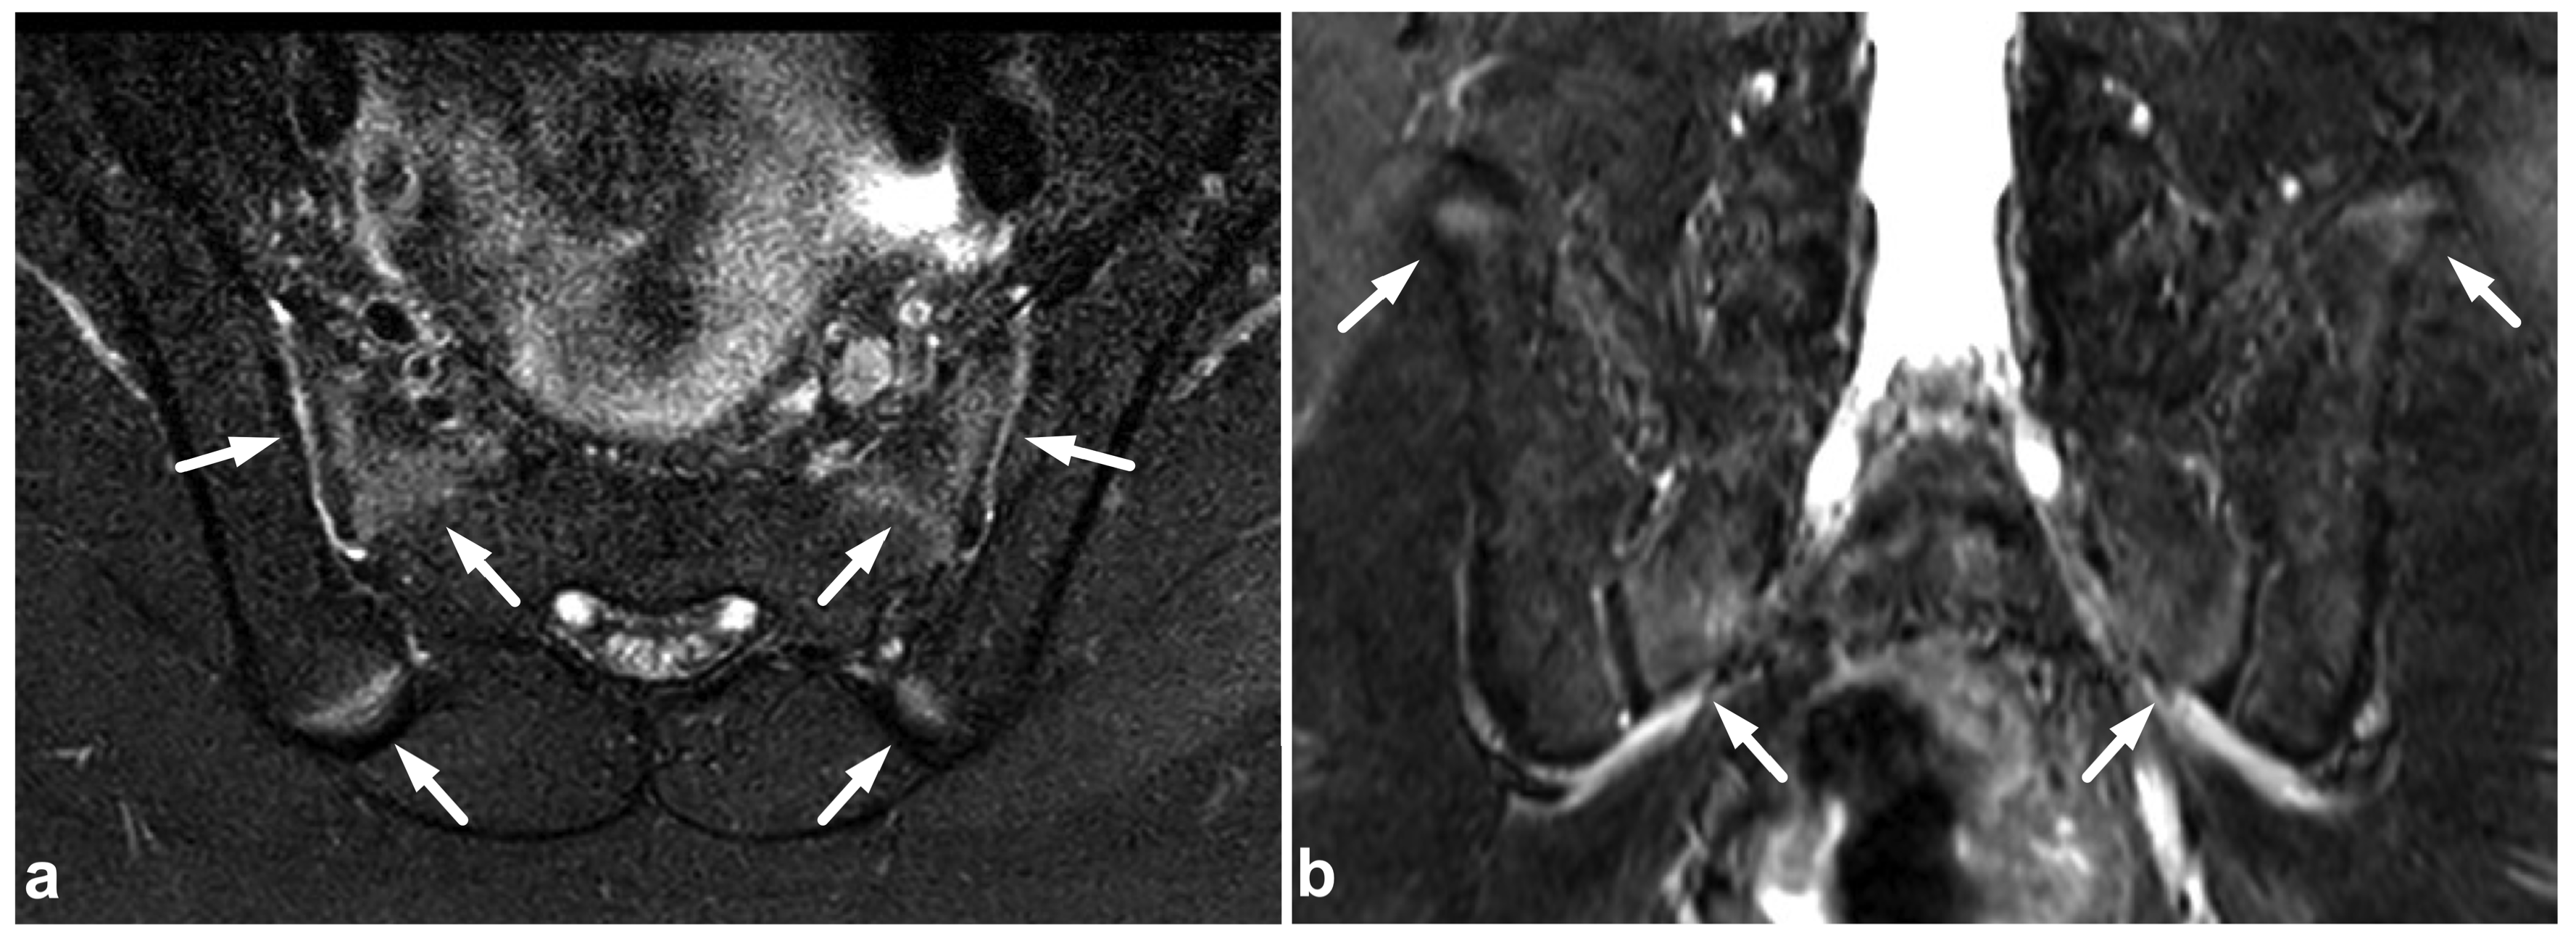

5.3. Nerve Plexus Injuries

5.4. Vascular Injuries